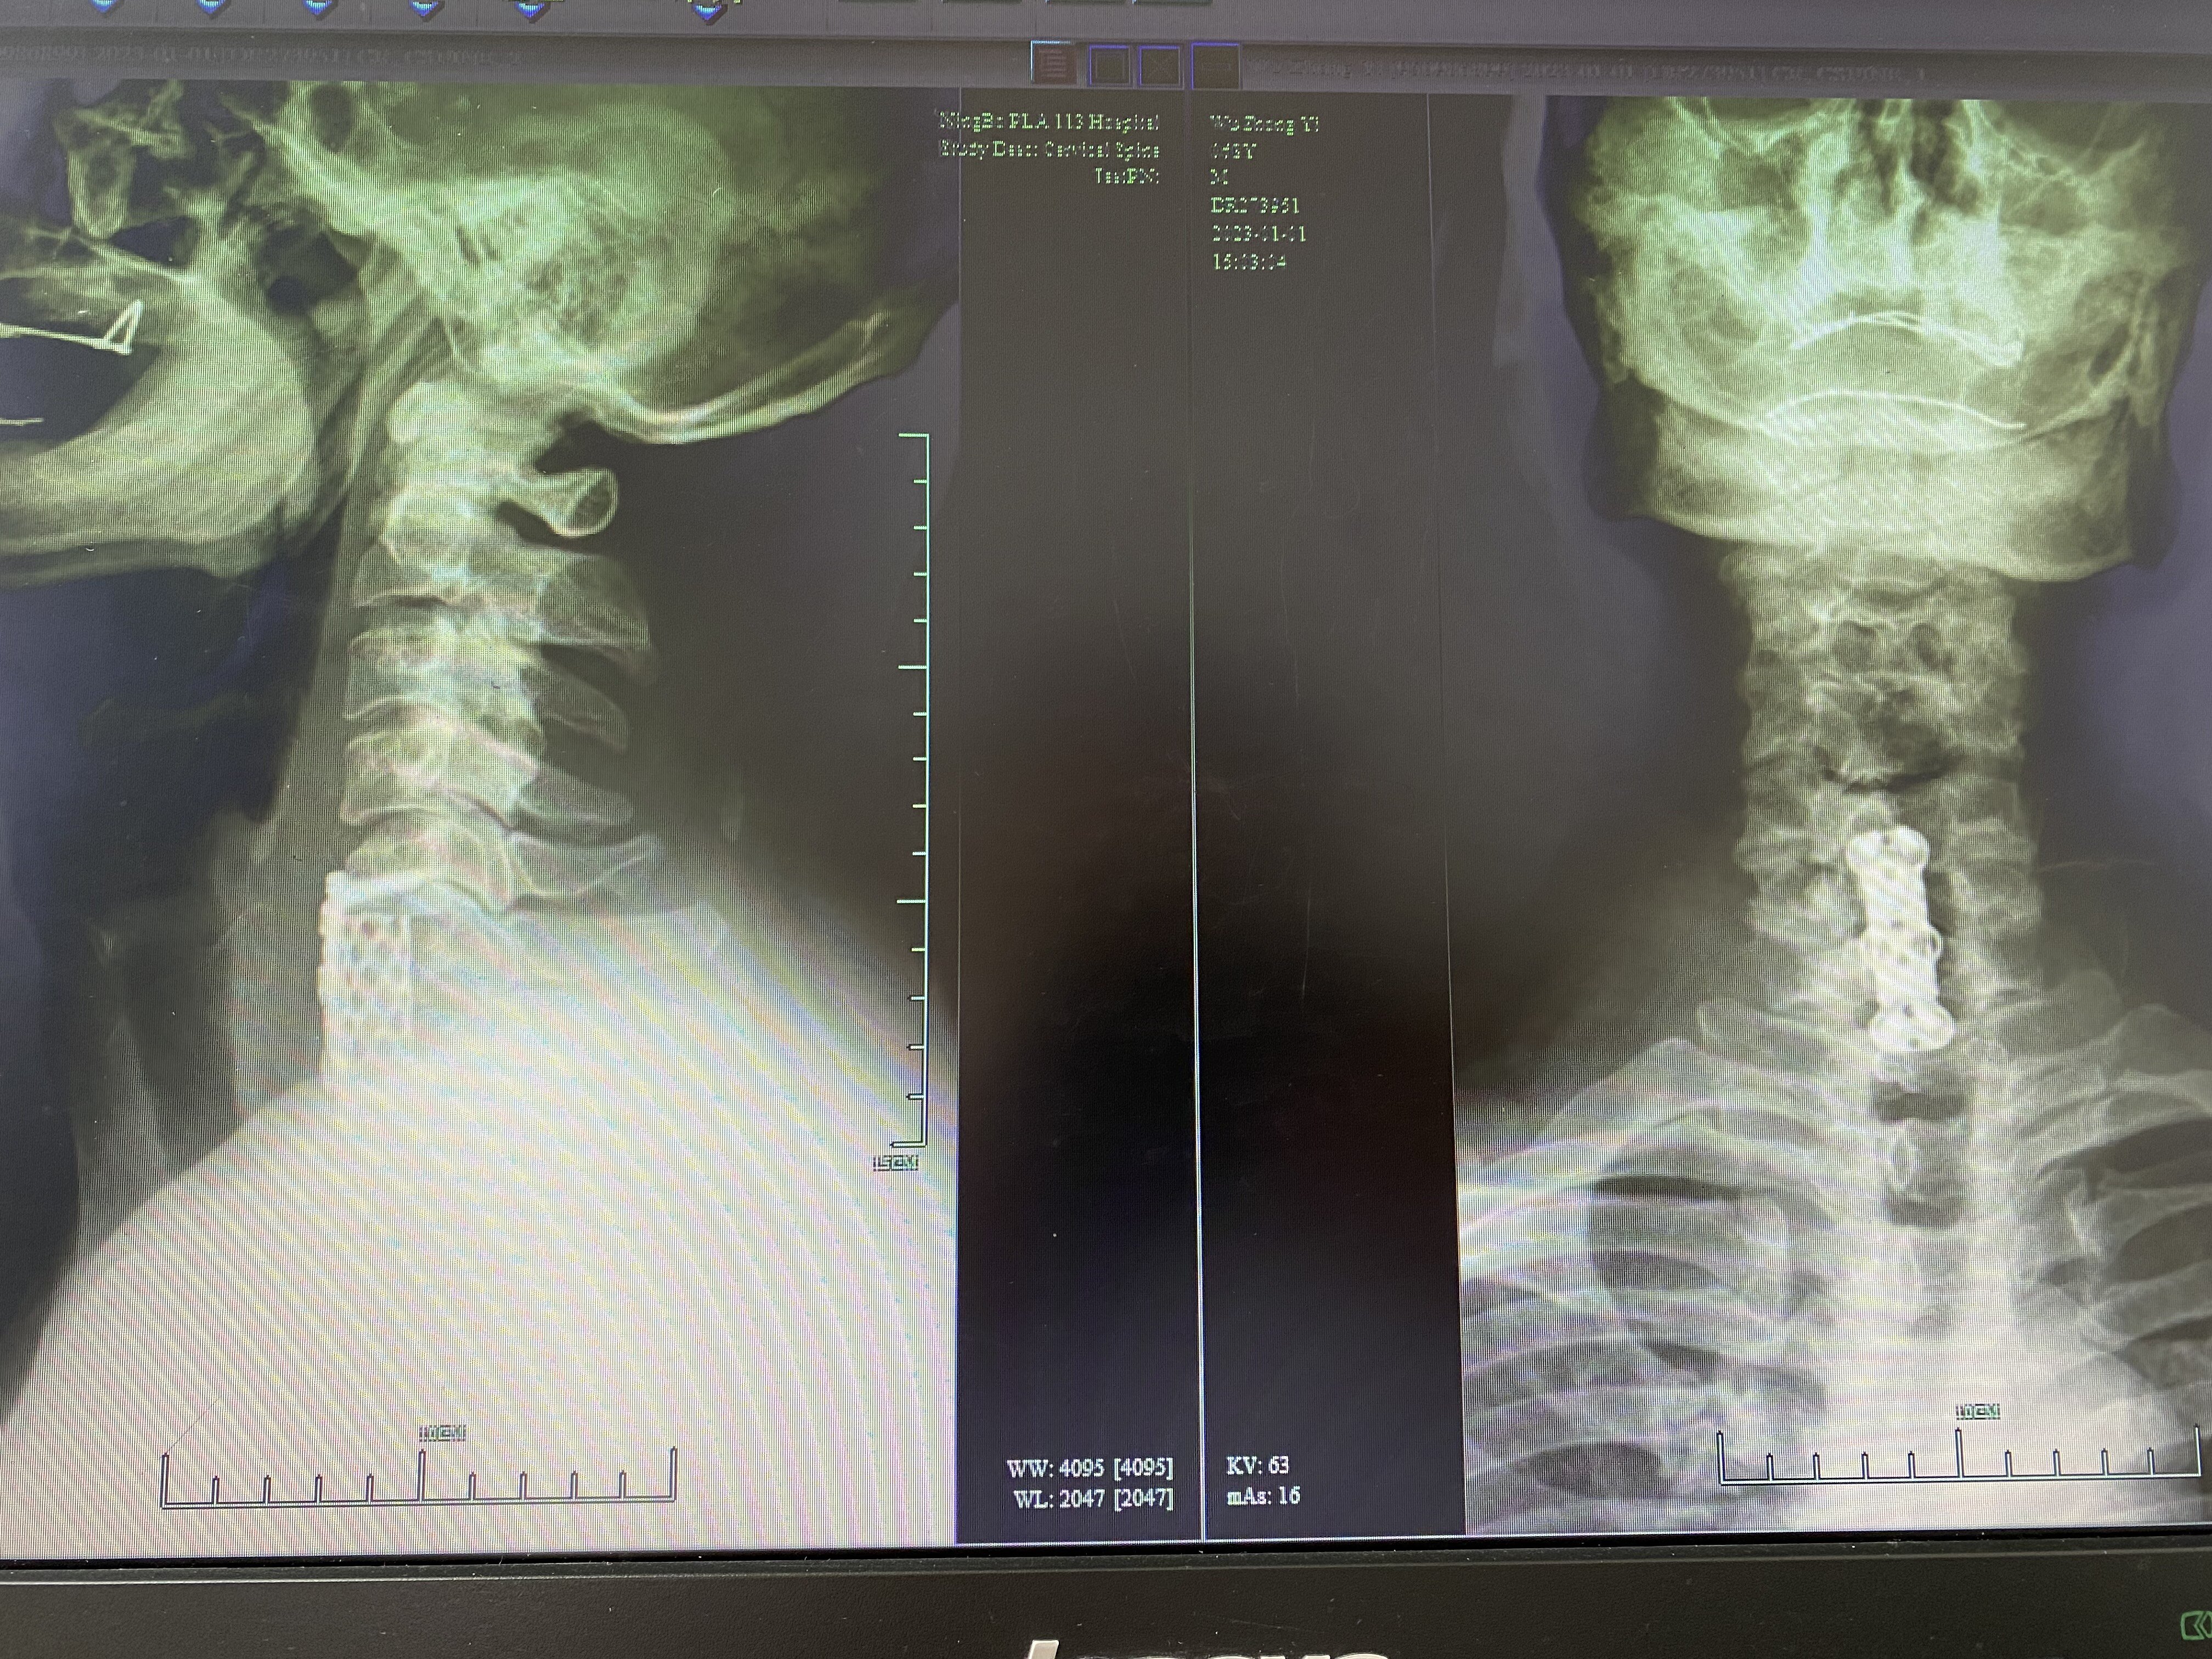

术后X线示:颈椎内固定位置良好、减压彻底